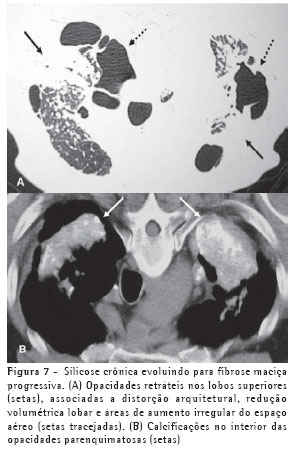

Os achados iniciais na TCAR consistem em micronódulos centrolobulares e subpleurais (Figura 4), menores que 0,5 cm. Com a evolução da doença estes micronódulos tendem à confluência, com formação de nódulos maiores (Figura 5), conglomerados (Figura 6) e, numa fase mais tardia, massas fibróticas, geralmente com calcificações e aumento irregular do espaço aéreo adjacente (Figura 7).(5)